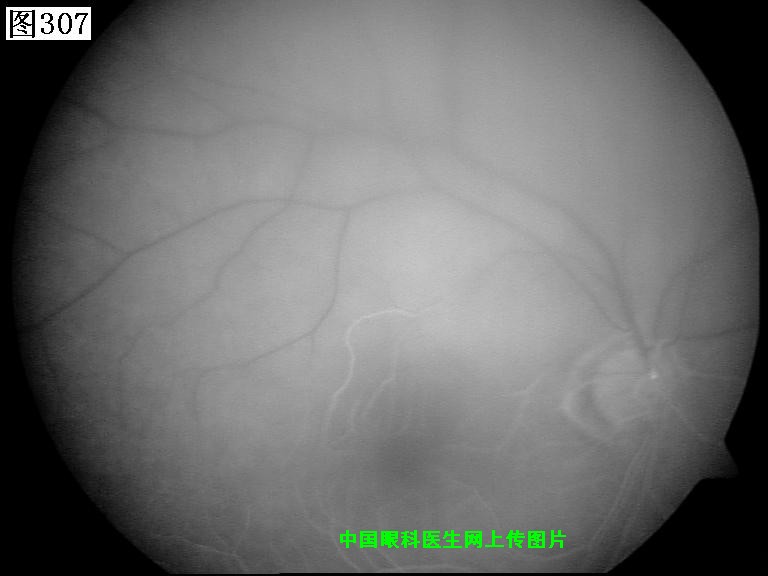

305 306 307 308